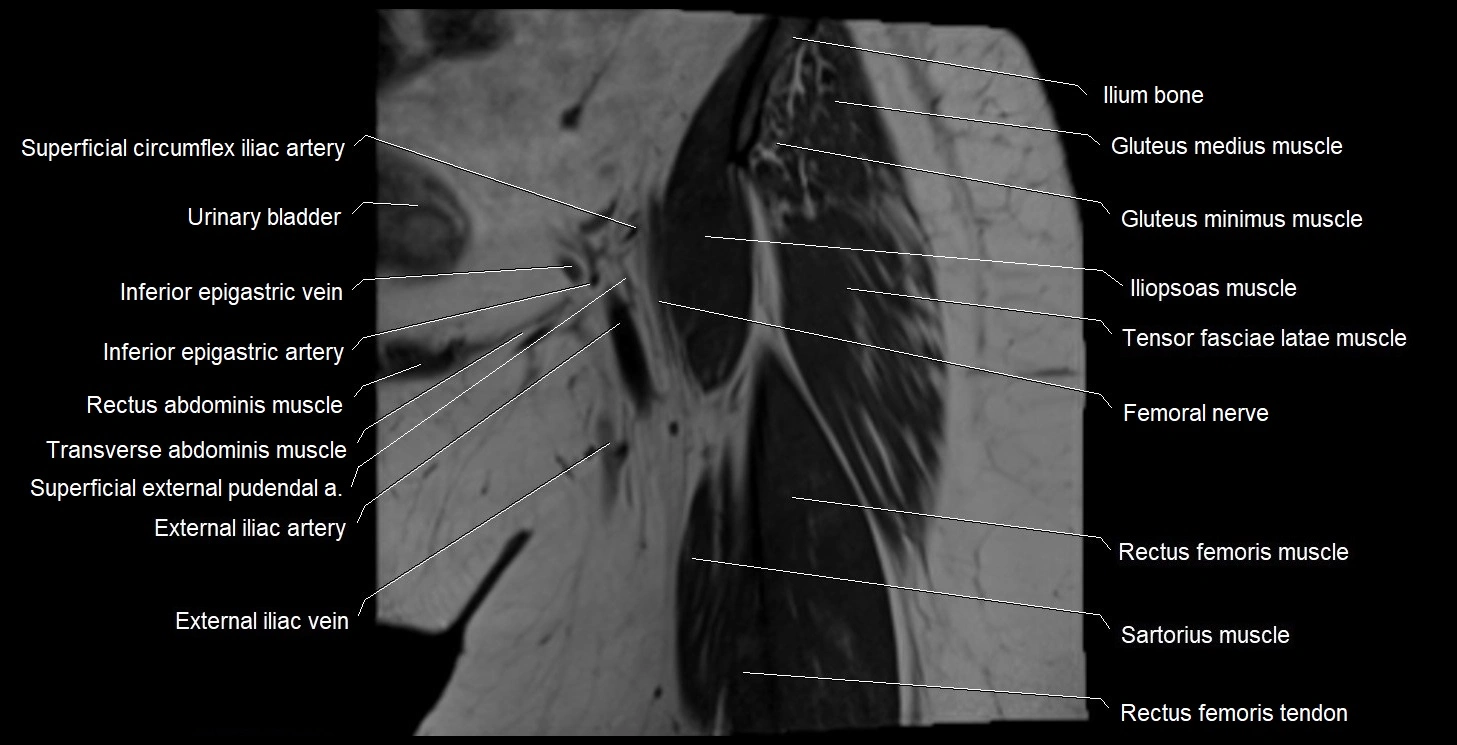

- External iliac artery

- External iliac vein

- Femoral nerve

- Iliopsoas muscle

- Inferior epigastric artery

- Inferior epigastric veins

- Rectus femoris muscle

- Rectus femoris tendon (Proximal tendon of rectus femoris)

- Sartorius muscle

- Superficial circumflex iliac artery

- Tensor fasciae latae muscle

- Urinary bladder